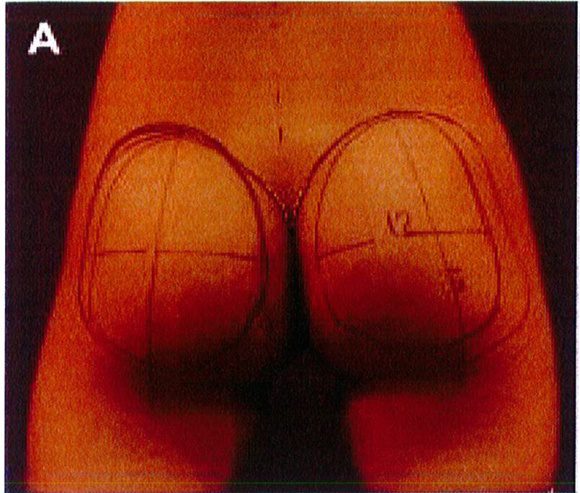

Những vấn đề mà chúng tôi đề cập trong kỹ thuật nâng mông dưới cân bao gồm các mốc giải phẫu được đánh dấu trên da trước phẫu thuật, kích thước và chất liệu khối implant.

tiêu bản như hình 4. Tiêu bản này phải được đặt chính giữa vùng mông, cách nếp lằn mông ít nhất 5cm và đường liên gai ít nhất 2cm (Hình. 5).

Bệnh nhân ở tư thế đứng, đánh dấu vị trí khối implant theo

Hình. 5. Đánh dấu vùng phẫu thuật phải tuân theo hình thể giải phẫu vốn có của từng bệnh nhân và đảm bảo rằng khối implant sẽ nằm phía ngoài xương cùng và cách nếp lằn mông khoảng 2-5 cm. (Trích từ de la Pena JA, Rubio OV, Cano JP, et al. Subfascial Gluteal Augmentation. Clin Plast Surg 2006;33:410; đã xin phép trước khi đăng tải.)